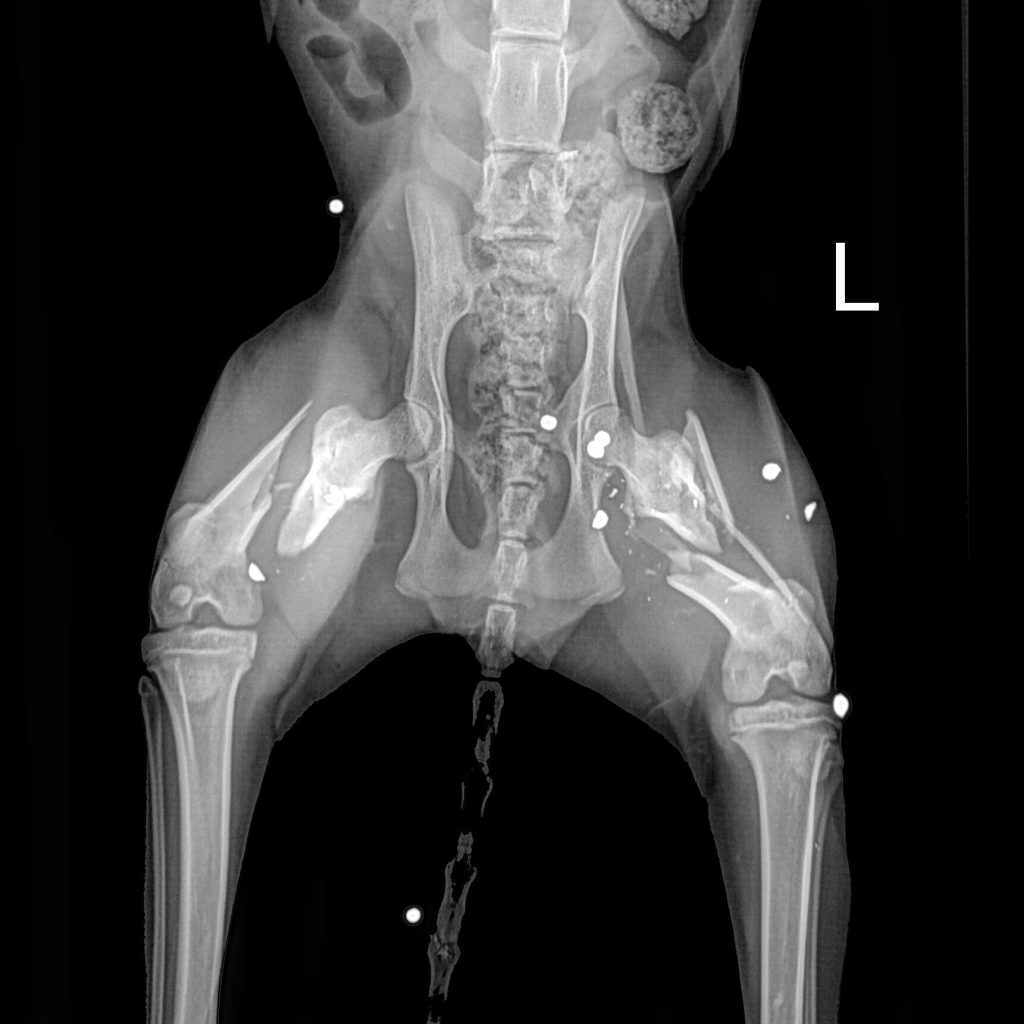

Today this cat arrived at the Richmond SPCA, and we named her Miracle. While Dr. David Molinas, our associate veterinarian, looked her over, she purred and made biscuits on the exam table with a level of affection that disguised the pain she must be experiencing. Radiographs from River Run Animal Hospital, where she was given supportive care yesterday, show metallic fragments that are likely birdshot scattered throughout her body, most highly concentrated in her pelvis and hind limbs. Both of her femurs, the large upper bones of the rear legs, are broken.

Though Dr. Molinas performs a number of complicated orthopedic surgeries for homeless animals we take in each year, Miracle's severe injuries require a specialist, and we have called upon Dr. Roy Barnes of James River Veterinary Surgery. Though the practice is normally closed on Fridays, Dr. Barnes and his surgical team agreed to take on Miracle's urgent case tomorrow. They hope to add a plate to her right femur, which has a single long fracture. Her left femur has broken into multiple pieces and will be more difficult to repair. Dr. Barnes will attempt to fix her left leg as well though we expect that healing will be challenging, and amputation of Miracle's rear leg remains a possibility.